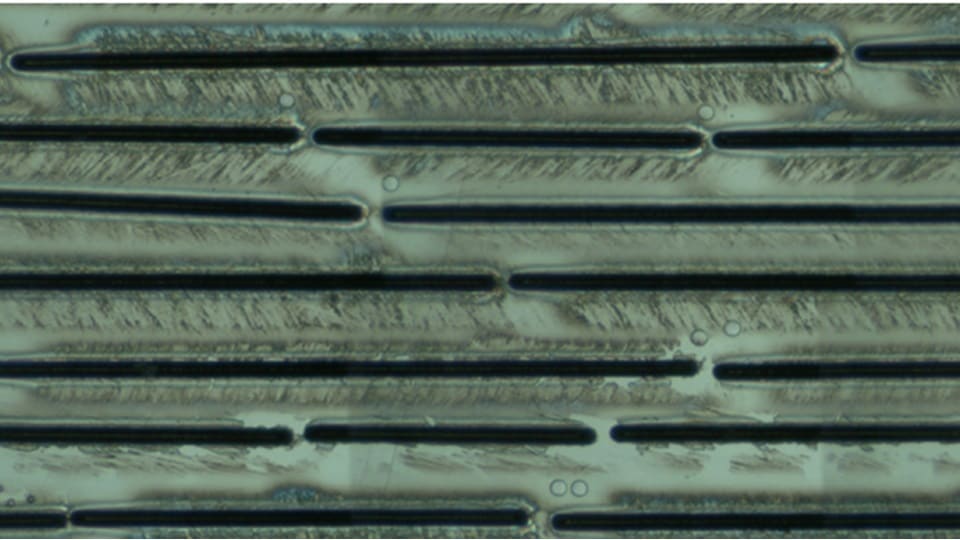

In the separate studies, the 8900 ICP-QQQ and 7900 ICP-MS instruments were coupled with an ESL213 Laser Ablation System equipped with an argon (Ar) mass flow controller (Elemental Scientific Lasers, Bozeman, MT, USA). Ar was used as the carrier gas and makeup gas instead of helium (He) gas in response to the shortage of He supplies in some countries.

The LA system was controlled directly from the Agilent ICP-MS MassHunter software via the ESL-developed ActiveView2 (AV2) plug-in for ICP-MS MassHunter (Figure 1), enabling fully integrated sample analysis, data processing, and reporting.